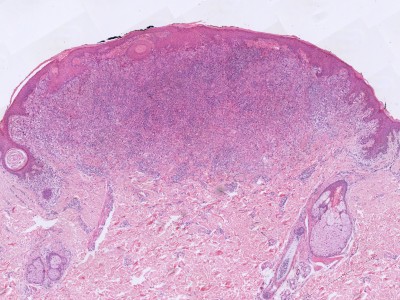

PA: Het karakteristieke PA kenmerk van Spitz tumoren

is de aanwezigheid van grote

spoelvormige cellen en/of

epithelioide cellen (melanocyten die lijken op keratinocyten).

Deze cellen zijn meestal gelegen in nesten hoog in de dermis, soms in de retelijsten

van de epidermis, soms in allebei. Er zijn verschillende histologische en morfologische

varianten van Spitz naevi, afhankelijk van welke chromosomale afwijking (tyrosine

kinase fusies, HRAS of MAP3K8 mutaties) er aanwezig is. Zie voor de correlatie

tussen de genetische afwijking, de klinische presentatie, en het histologisch

beeld het overzichtsartikel van Urso C. uit 2023.

De klassieke benigne

Spitz naevi zijn scherp begrensde symmetrische wigvormige laesies opgebouwd

uit grote junctionele (op de overgang epidermis-dermis) en dermale nesten van

spoelvormige en/of epithelioide melanocytaire cellen. Deze cellen zijn groot,

met veel bleek of matglas-achtig aankleurend cytoplasma en soms fijnkorrelig

pigment. Er is wat kern pleomorfisme, maar weinig of geen mitosen. De junctionele

nesten zijn loodrecht op de epidermis georiënteerd en vaak omgeven door spleetvormige

ruimten, dit zijn artefacten die ontstaan tijdens de bewerking van de coupe.

Melanocyten kunnen opstijgen in de epidermis (ascensie, synoniem pagetosis,

pagetoide verspreiding), meestal beperkt tot de onderste helft van de epidermis,

en transepidermale elininatie van melanocyten komt voor. Op de dermo-epidermale

overgang kunnen bij klassieke Spitz-naevi PAS-positieve eosinofiele hyaline

globuli voorkomen die

Kamino bodies worden genoemd.

Verder is er soms een perivasculair lymfocytair infiltraat. Zie ook de

ingescande

PA-coupe van de

afdeling

pathologie van de University of Toronto, en de ingescande coupes uit het

LUMC hier onder: